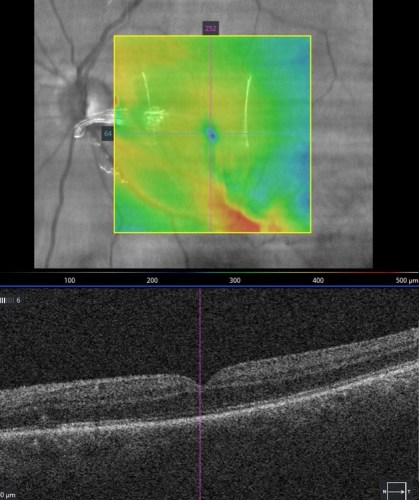

I thought that those of you who have been brave enough to see the graphic photos from my operating team might be interested to see, some non surgical photos of the retina pre and post surgery to round out your ophthalmic education.